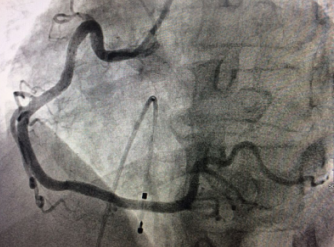

近日,在我院心血管内科病房内,70岁的患者张大爷康复出院,患者及家属握着医生的手连声道谢。谁能想到,这样一个思维清晰、开朗健谈的老人,10多天前还因为急性ST段抬高型心梗(急性心肌梗塞的一种)濒临死亡,在心脏导管室内进行争分夺秒的抢救呢! 突发胸痛3小时 70岁老人病情危急 家住江...